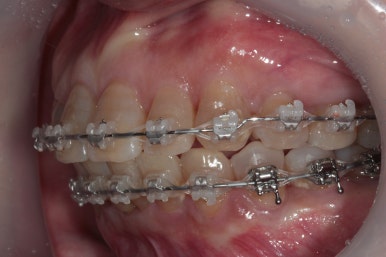

교정 시작하고 6개월만에 치아배열이 다되어갑니다.

요새 유행하는 인비절라인 (투명교정) 의 경우 치료 기간에 가장 중요한 것이 환자의 협조도입니다.

그런 면에서 고정식 브라켓을 치아에 붙이고 와이어를 이용해서 교정을 해내는 전통적 스타일의 클리피씨 교정치료는 치료기간을 상당히 단축시킬 수 있다는 장점이 있습니다.

요새 교정 브라켓은 하얀색이 많고, 사실 교정치료 받는다는 것이 부끄러운 것이 아닌 세상입니다.

기왕 하실거라면.. 치료기간이 불확실한 인비절라인보단 고정식 장치를 사용하는 클리피씨 교정치료를 권해드리겠습니다.

이제 정말 많이 배열이 완성되었습니다. 아래 앞니를 배열시키느라 시간이 조금 더 걸렸던 것 같아요.